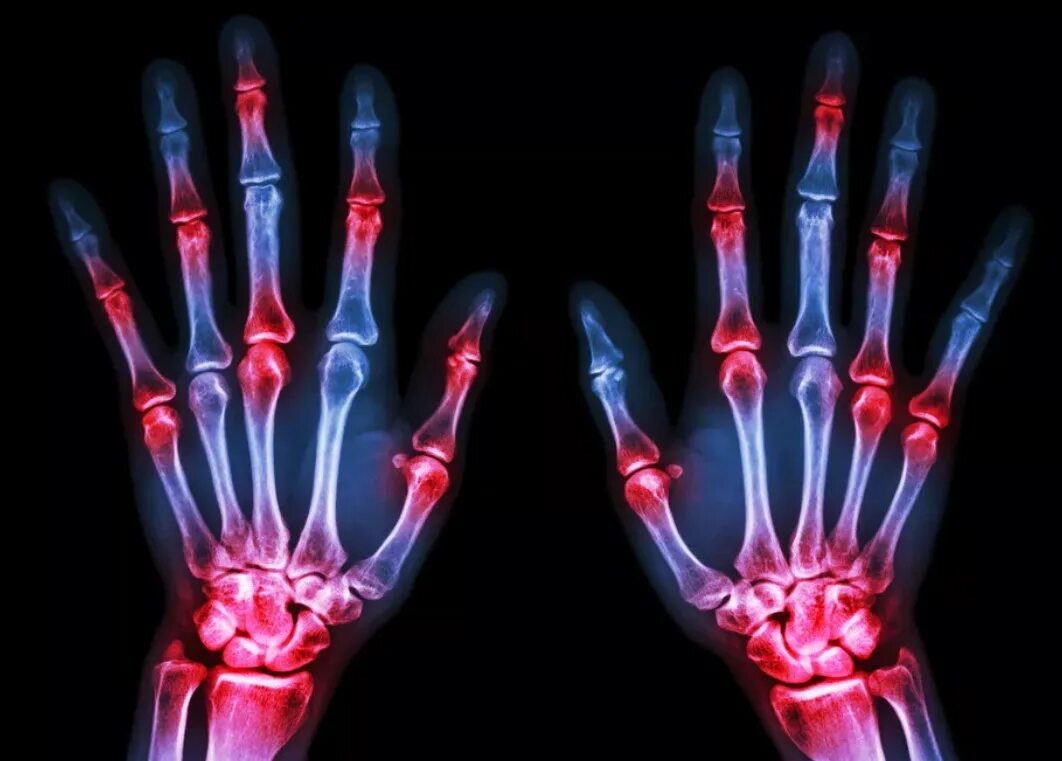

Болят суставы кисти ног